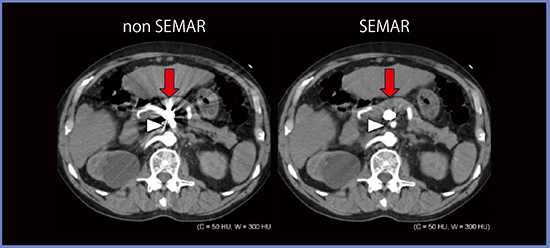

図4は,70歳代,男性,膵十二指腸動脈瘤に対してcoil packing術を施行した症例で,通常の画像では金属アーチファクトで確認できないが,SEMARによってアーチファクトが低減することでコイルの背側の動脈も確認でき,フォローアップが可能になる。

動脈瘤のコイル塞栓術後評価におけるSEMARの役割について,定性評価と定量評価を行った。定性評価は視覚スコア4段階で,定量評価はコイルの周囲に複数のROIを設定してSDを計測し,5か所を平均化して行った(図5)。結果は,定量評価ではノイズはnon SEMAR65±33,SEMAR30±10,アーチファクトは164±55,10±19,定性評価は視覚スコアで1.0±0.0,3.4±0.6と劇的に改善することが確認できた。

図4 膵十二指腸動脈瘤に対するcoil packing術後(70歳代,男性)4)

図5 動脈瘤のコイル塞栓術後評価におけるSEMARの役割4)